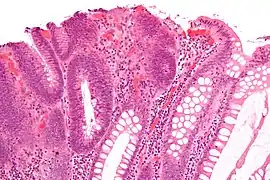

| Hyperplastic polyp | Colorectal (unless otherwise specified) | Serrated unbranched crypts | if polyps are more than 100 | ![]() |

Serrated polyposis syndrome |